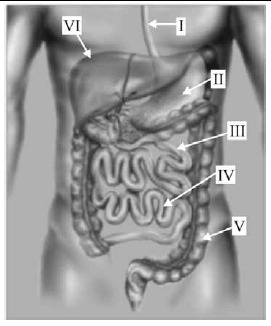

Com base na figura acima, que representa o trato digestório humano, julgue os itens de 71 a 77.

Os ácidos graxos de cadeia curta produzidos na estrutura indicada por V tanto aumentam a absorção de eletrólitos e água quanto reduzem a carga osmótica de açúcares mal digeridos.